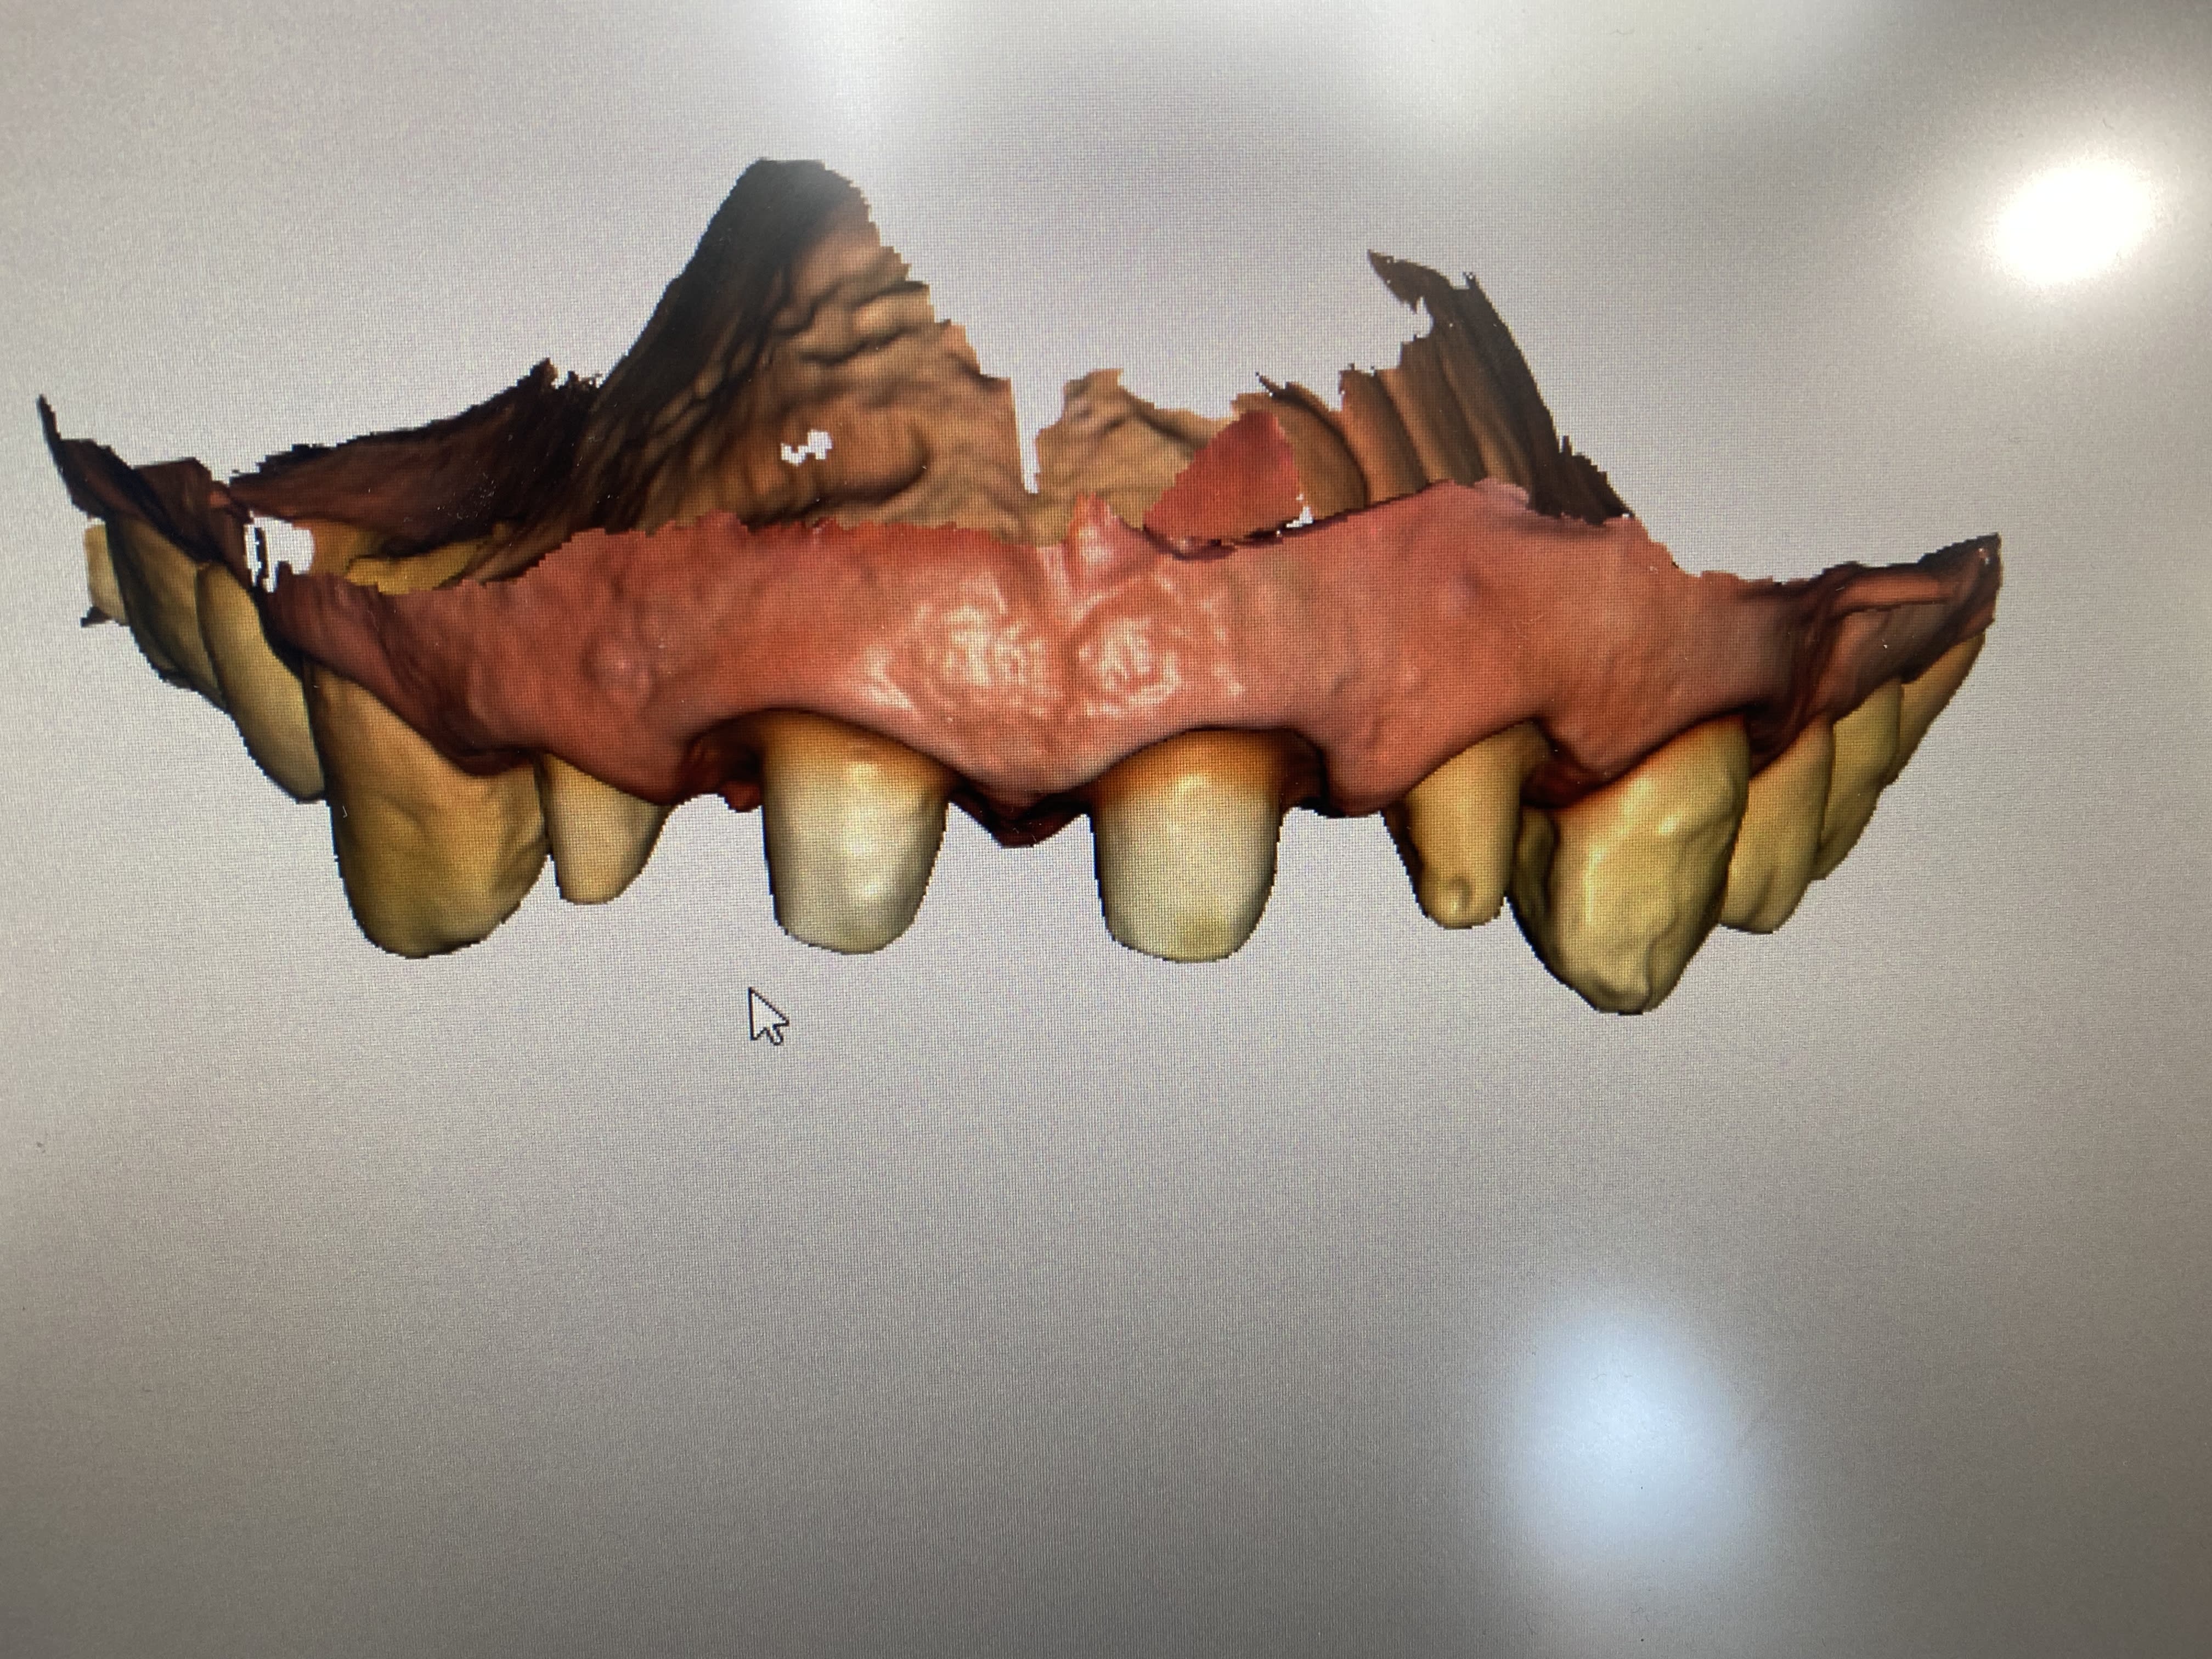

Cas dont je suis fier, et qui m'énerve un peu.

Patiente que j'ai vaguement vue en 2019 pour 3 bricoles, rien de notable.

Un peu après le premier confinement (05 2020 donc), commence à ressentir des douleurs diffuses maxillo faciales; son généraliste lui prescrit des antibiotiques pour une sinusite.

Rebelote 6 mois plus tard, cette fois elle se rend aux urgences dentaires, qui ne voient rien et la renvoient vers un orl.

L'orl la voit, lui fait faire une irm, diagnostique un quelconque SADAM ou équivalent, lui prescrit de la gymnastique mandibulaire et , coup de chance en fait, lui dit d'aller voir ma gueule pour faire une gouttière.

Entre temps, re "sinusite", re antibios, re soulagement temporaire.

Bref, elle arrive ce soir pour une consult occluso/gouttière, et heureusement que je ne fais pas trop confiance à personne, je reprends tout du début.

Evidemment, aucun signe douloureux musculaire, ATM parfaitement fonctionnelles, mais une 37 qui ne réagit ni au froid, ni au fraisage, et finalement ni à l'ouverture de chambre.

1 an que ça durait ces conneries, pour un diag simplissime, ça pique toujours un peu. A mon avis, ça va vite aller mieux. On verra hein?